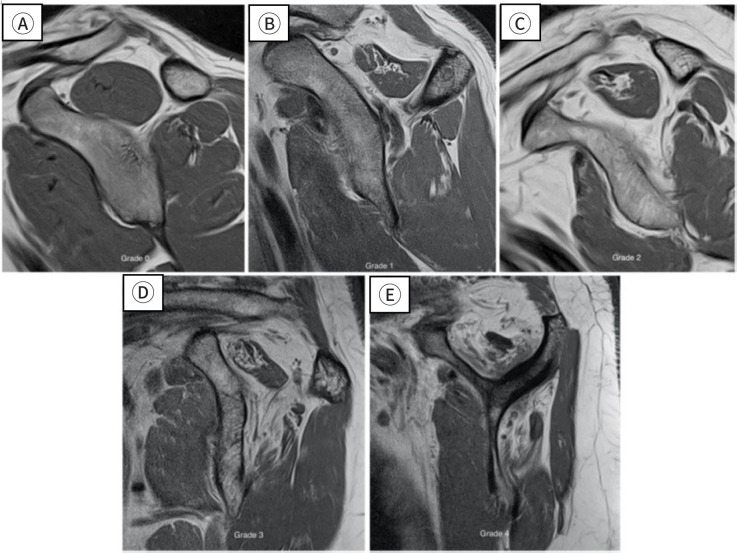

肩部疾病,包括粘连性囊炎、肩袖撕裂和肩关节骨关节炎,可严重损害老年成人患者的日常活动。本综述旨在探讨老年患者这些肩关节疾病的影像学表现,为准确诊断和有效治疗提供见解。粘连性囊炎,俗称冻肩,导致疼痛和活动受限,从而引起肩关节功能障碍。最近诊断技术的进步极大地提高了通过放射学评估诊断这种疾病的敏感性和准确性,包括MRI,磁共振关节成像(MRA)和高分辨率超声。肩袖疾病是老年人的另一个常见问题,50%-80%的病例发生全层撕裂。MRI和MRA在识别肩袖撕裂方面都是高度敏感和特异性的。此外,超声在检测冈上肌腱撕裂方面具有很高的敏感性和特异性。虽然肩关节骨关节炎不太常见,但其晚期可严重影响上肢的功能。x线平片通常是评估这类骨关节炎的首选成像技术。随着病情的恶化,CT被用于测量关节盂骨丢失、关节盂形态和关节盂倾斜度,这对于精确的手术计划至关重要。每种成像方式都有其独特的优势:x线平片用于初始结构评估,超声检查用于软组织的实时评估,MRI/MRA用于详细可视化囊和肌腱病变,CT用于精确的骨骼分析。

Shoulder diseases, including adhesive capsulitis, rotator cuff tear, and osteoarthritis of the glenohumeral joint, can significantly impair daily activities in older adult patients. This review aims to examine the radiologic findings associated with these shoulder conditions in older patients, providing insights for accurate diagnosis and effective treatment. Adhesive capsulitis, commonly known as frozen shoulder, leads to pain and restricted movement, thereby causing shoulder dysfunction. Recent advances in diagnostic technology have greatly enhanced the sensitivity and accuracy of diagnosing this condition through radiologic evaluations, including MRI, magnetic resonance arthrography (MRA), and high-resolution ultrasound. Rotator cuff disease is another frequent issue in older adults, with full-thickness tears occurring in 50%-80% of cases. Both MRI and MRA are highly sensitive and specific in identifying rotator cuff tears. Additionally, ultrasonography is recognized for its high sensitivity and specificity in detecting tears of the supraspinatus tendon. Although osteoarthritis of the glenohumeral joint is less commonly prevalent, its advanced stages can severely affect the function of the upper extremity. Plain radiography is typically the first imaging technique used to assess this type of osteoarthritis. As the condition worsens, CT is utilized to measure glenoid bone loss, glenoid version, and inclination, which are crucial for accurate surgical planning. Each imaging modality provides distinct benefits: plain radiographs for initial structural assessment, ultrasonography for real-time evaluation of soft tissues, MRI/MRA for detailed visualization of capsular and tendinous lesions, and CT for precise bony analysis.